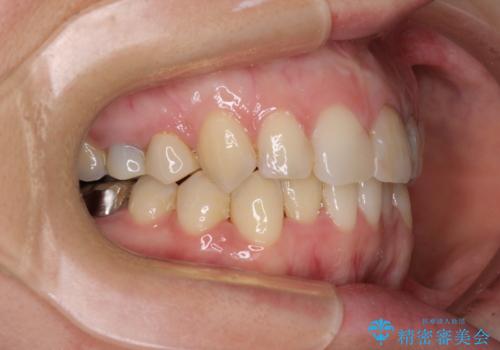

主に下顎歯列全体の後方移動とIPR(歯と歯の間を削る)によってデコボコが解消するように設計し、インビザラインにより治療を行うこととしました。

矯正治療後半に下顎左右奥歯をセラミッククラウンにて補綴し、その後インビザラインによる歯列の仕上げを行うこととしました。

下顎前歯の叢生が速やかに改善されたため、1年3か月で治療を終えることができました。

下顎前歯は後戻りを起こしやすいため、舌側を細いワイヤーで固定することで後戻り対策を行っています。